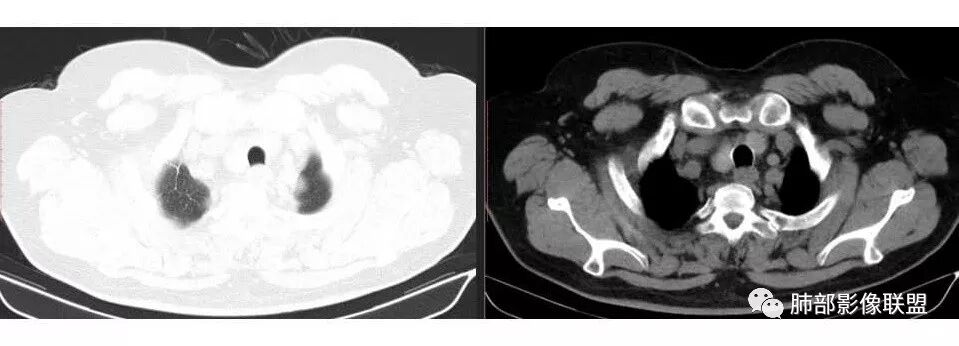

市医院--时建文: 右肺门占位性病变伴纵隔淋巴结肿大,鳞癌?小细胞癌?淋巴瘤待除外,右肺上叶结核。

wkj: 40岁以上吸烟男,右肺上叶新生物,纵隔新生物大于肺新生物,纵隔呈融合,冰冻,气管外压,血管疑似未受累,仅包绕,考虑小细胞。

张帅: 患者以肢体无力就诊,既往有吸烟史,胸CT:右肺门占位性病变,密度不均,病灶内病灶内支气管明显狭窄,走行僵硬,病灶边缘光滑,呈浅分叶,未见明显毛刺,对中叶支气管明显挤压。右肺内可见散在片状实变影,前纵隔淋巴结明显肿大,内可见低密度区,2r 4r 7 10r淋巴结明显肿大。诊断考虑恶性方向,肺癌(小细胞)并纵隔肺门淋巴结转移?淋巴瘤?

1.右肺上叶不规则结节影,右肺门及纵隔多结节并形成巨大块影,密度均匀,沿途支气管明显狭窄。

原发灶小或隐匿,肺门纵隔淋巴结异常增大,所谓“娘小崽大”常见于肺小细胞癌!